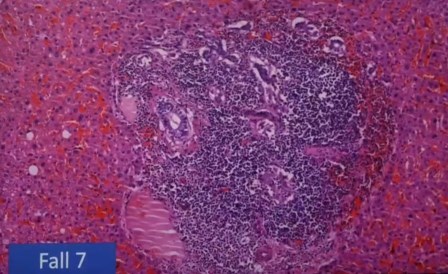

Aglomeración de linfocitos alrededor de un vaso

Fenómenos del sistema autoinmune desconocidos, Sjörgen, Hashimoto extremadamente raro y se ve en estos fallecidos varias veces, lo cual es alarmante. Además, se observa una aceleración de crecimiento de tumores.

«Esto no es autolisis y lo vemos una y otra vez, con desprendimiento del endotelio de los vasos, entotelitis», exclama el científico. Terrible.

«Antes no lo había visto, y yo he visto mas de 40 mil autopsias y 500 mil biopsias, estas células que se han desprendido no es autolisis, porque hay también eritrocitos, que son las células largas, y no pueden estar allí después de la autolisis y lo vemos una y otra vez. Hay desprendimiento de células endotélicas», detalla.

Esta aglomeración está en investigación